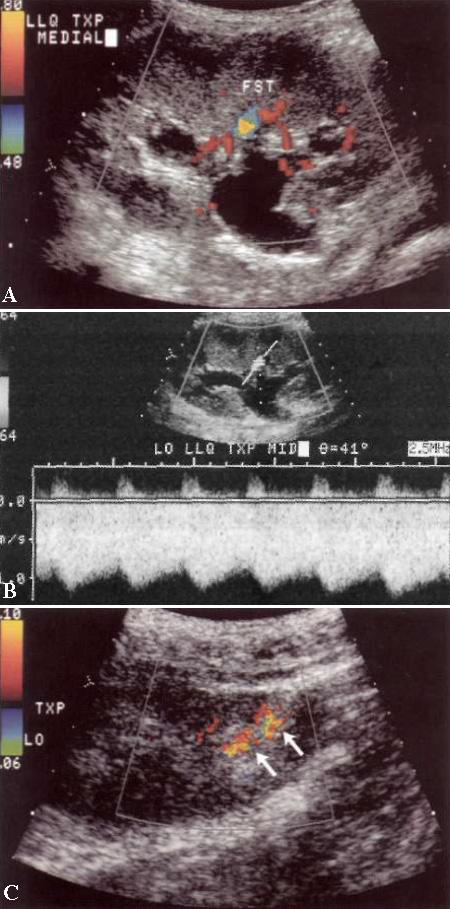

УЗИ: Ложная аневризма артериовенозной диализной фистулы

Фото 2. Ложная аневризма артериовенозной диализной фистулы. А – цветовая допплерограмма демонстрирует ложную аневризму, которая исходит из артериовенозной диализной фистулы. В – спектральная допплерограмма демонстрирует кровоток внутрь и наружу из аневризмы характерной двухфазной формы с полным обратным током в диастолу